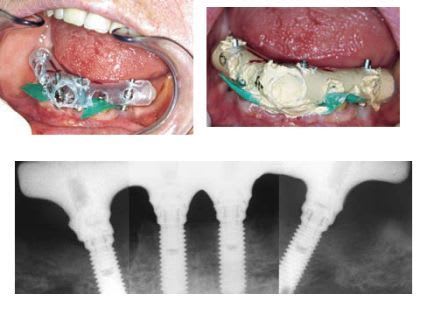

pick-up ou repositionnement

photo emp platre pour pib complet